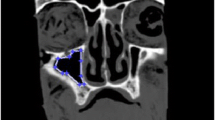

Acoustically driven nebulized drug delivery (acoustic aerosol delivery) is the most efficient noninvasive technique for drug delivery to maxillary sinuses (MS). This method is based on the oscillation of the air plug inside the ostium to transport drug particles from the nasal cavity (NC) to the MS. The larger the wavelength of the air plug oscillation in the ostium, the greater the penetration of drug particles to the MS. However, using this technique, the maximum drug delivery efficiency achieved to date is 5%, which means 95% of the aerosolized drugs do not enter the MS and are wasted. Since the largest amplitude of the air plug oscillation occurs at its resonance frequency, to achieve an improved MS drug delivery efficiency, it is important to determine the resonance frequency of the nose–sinus combination accurately. This paper aims to investigate the impact of geometrical parameters on the resonance frequency of the nose–sinus model. Both experimental and computational acoustic models, along with the theoretical analysis, were conducted to determine the resonance frequency of an idealized nose–sinus model. The computational modeling was carried out using computational fluid dynamics (CFD) and finite element analysis (FEA), whereas in the analytical solution, the mathematical relationships developed for a conventional Helmholtz resonator were employed. A series of experiments were also conducted to measure the resonance frequency of a realistic NC–MS combination. The results demonstrated a good agreement between the experimental and CFD modeling, while the FEA and theoretical analysis showed a significant deviation from the experimental data. Also, it was shown that the resonance frequency of the idealized nose–sinus model increases by up to twofold with increasing the ostium diameter from 3 to 9 mm; however, it has an inverse relationship with the ostium length and sinus volume. It was also reported that the resonance frequency of the nose–sinus model is independent of the NC width and MS shape.

Pourmehran, O., Arjomandi, M., Cazzolato, B. et al. The impact of geometrical parameters on acoustically driven drug delivery to maxillary sinuses. Biomech Model Mechanobiol 19, 557–575 (2020). https://doi.org/10.1007/s10237-019-01230-5